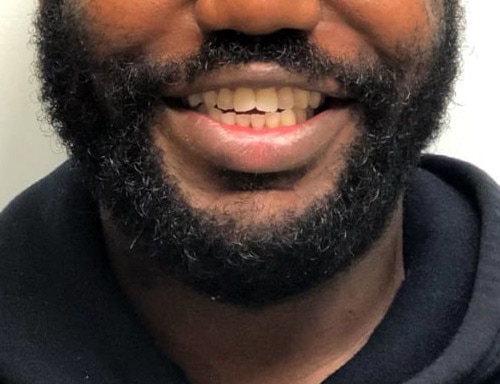

For a standard bite, the top teeth contact and slightly overlap the bottom teeth all the way around the mouth. In an open bite, there is a space between the upper and lower front teeth and they do not overlap. Because the front teeth don’t touch, it can put extra pressure on the teeth that do make contact, leading to problems now and later in life.

- Anterior (Front) open bite: This is where your front teeth do not meet and is the most common and noticeable form of open bite. Anterior open bites can include just two teeth not contacting or several teeth not touching.